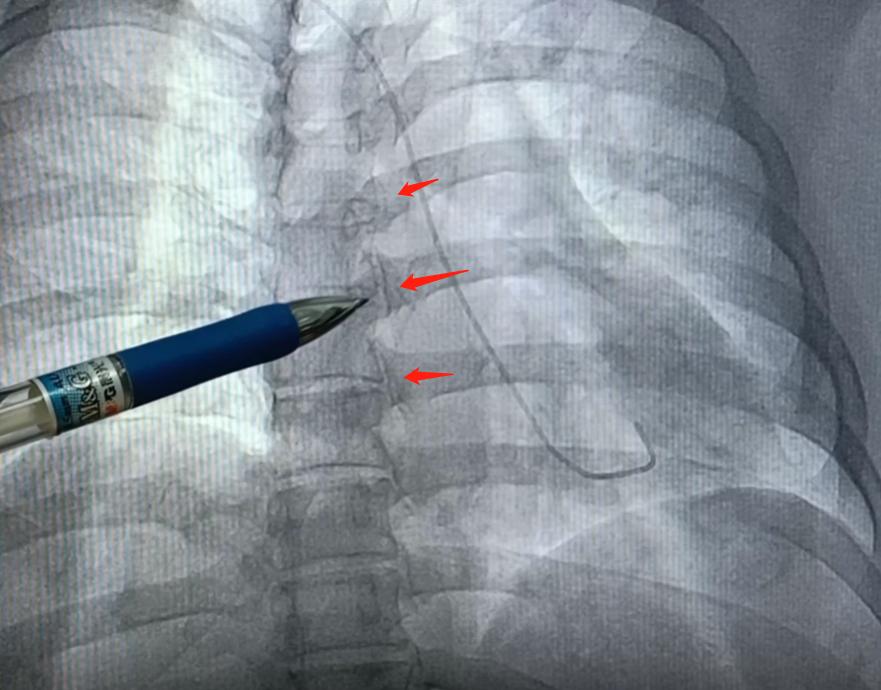

造影检查可以看出,前降支的开口和近端有一个95%的狭窄,局部伴有血栓存在。回旋支和右冠状动脉虽然有一些斑块,但是没见到明显的狭窄的地方,血流也正常,引起心梗的主要位置就是前降支的近端。